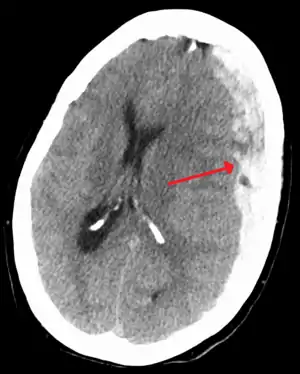

| Subdural hematoma as marked by the arrow with significant midline shift | |